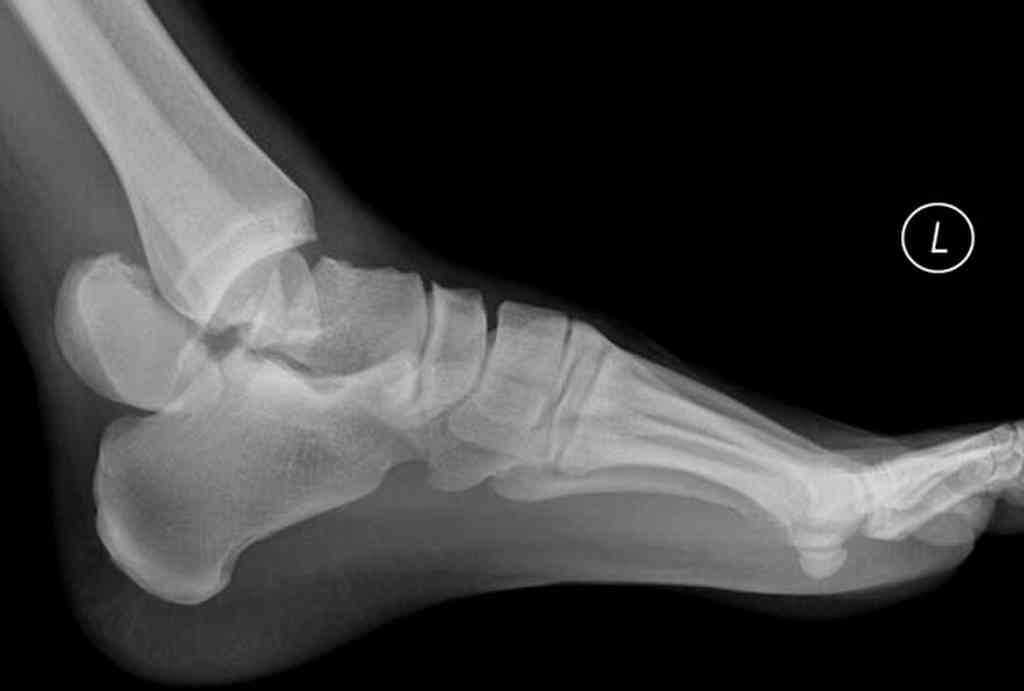

- МРТ либо рентгенография ступни, что позволяет увидеть наличие поражения кости (делают рентген в 2 проекциях – боковой, прямой),

Второй этап характеризуется уплощением сводов, деформацией стопы. Во время рентгенограммы хорошо просматриваются костные фрагменты.

Деформация костей стопы достаточно хорошо видна. При осмотре врач может поставить диагноз без дополнительного обследования.

При помощи рентгенографии можно увидеть сильные изменения формы стопы. Существует риск внезапных переломов, вывихов. Пальцы имеют клювовидную форму. Стопа Шарко при сахарном диабете на данной стадии еще поддается лечению.